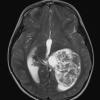

NEOPLASMS (NON-GLIAL NON-NEURONAL)

Choroid plexus papilloma (6)